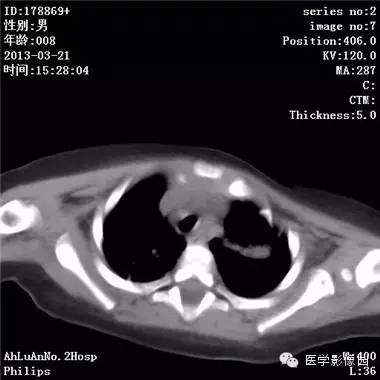

【病例】支气管异物1例CT影像表现

患儿男,8个月,呛咳,发热一周。实验室检查白细胞及中性粒细胞增高。

两肺肺纹理增多、增粗,右肺可见斑片状、片絮状模糊影,边界欠清;左肺上叶见楔形高密度影,内可见支气管征,尖端指向肺门;左肺下叶肺野透亮度增强;另见左肺主支气管内可见块状软组织密度影。

支气管异物(花生米)伴两肺炎症(追问病史,患儿奶奶层于一周前喂食患儿花生米,当时疑似“呛进去”,后来见好了也就没留意)。